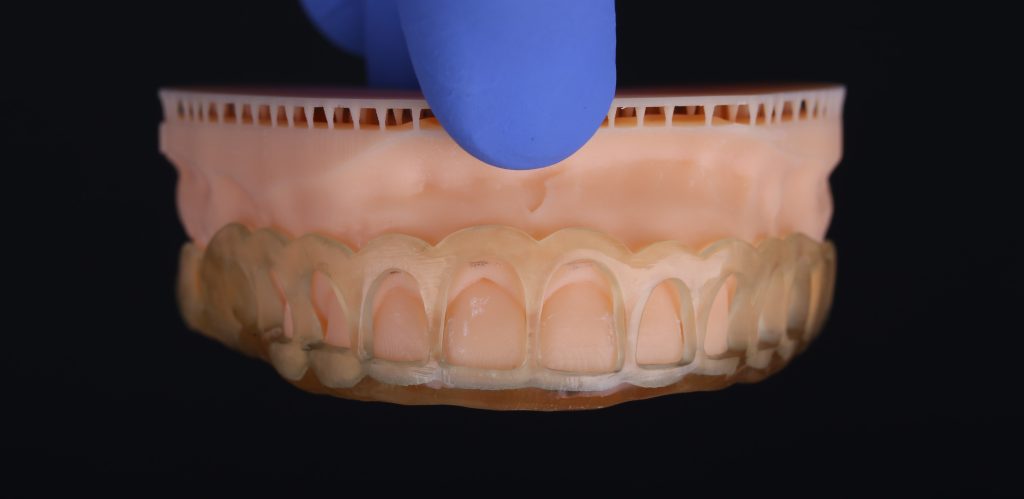

The future gum contour was determined using diagnostic wax-up

Verification of the accuracy of template positioning on the teeth

The final result of comprehensive prosthetic rehabilitation with Diagnocat AI